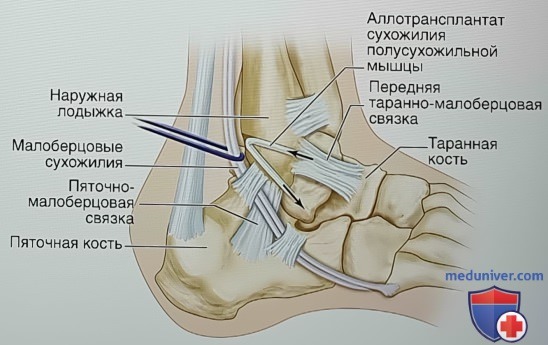

Анатомия голеностопа: Сухожилия и их строение